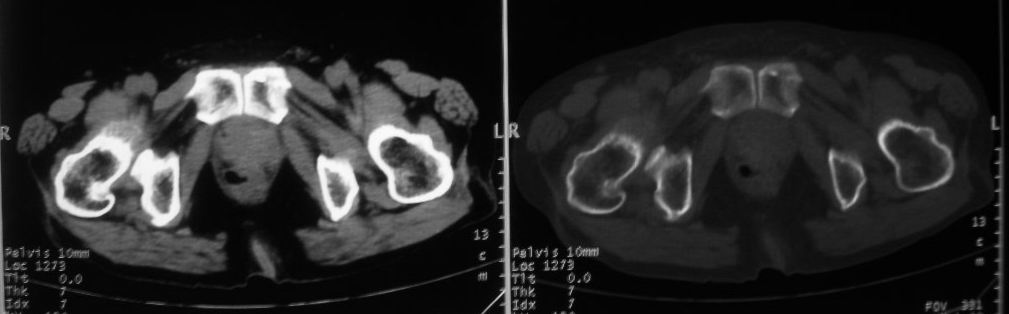

以下是引用zjzjr在2008-10-3 12:59:00的发言:[br]前列腺癌伴左髂骨\\腰椎转移可能性大.

以下是引用卜一在2008-10-3 13:40:00的发言:[br]前列腺癌!左髂骨\\腰椎转移?建议行全身骨扫描!

以下是引用深泽交通医院在2008-10-3 15:33:00的发言:[br]前列腺实性增大伴分叶状,与包膜间隙境界不清;椎体松质区间结节样密度影,考虑:前列腺癌,并椎体成骨性转移